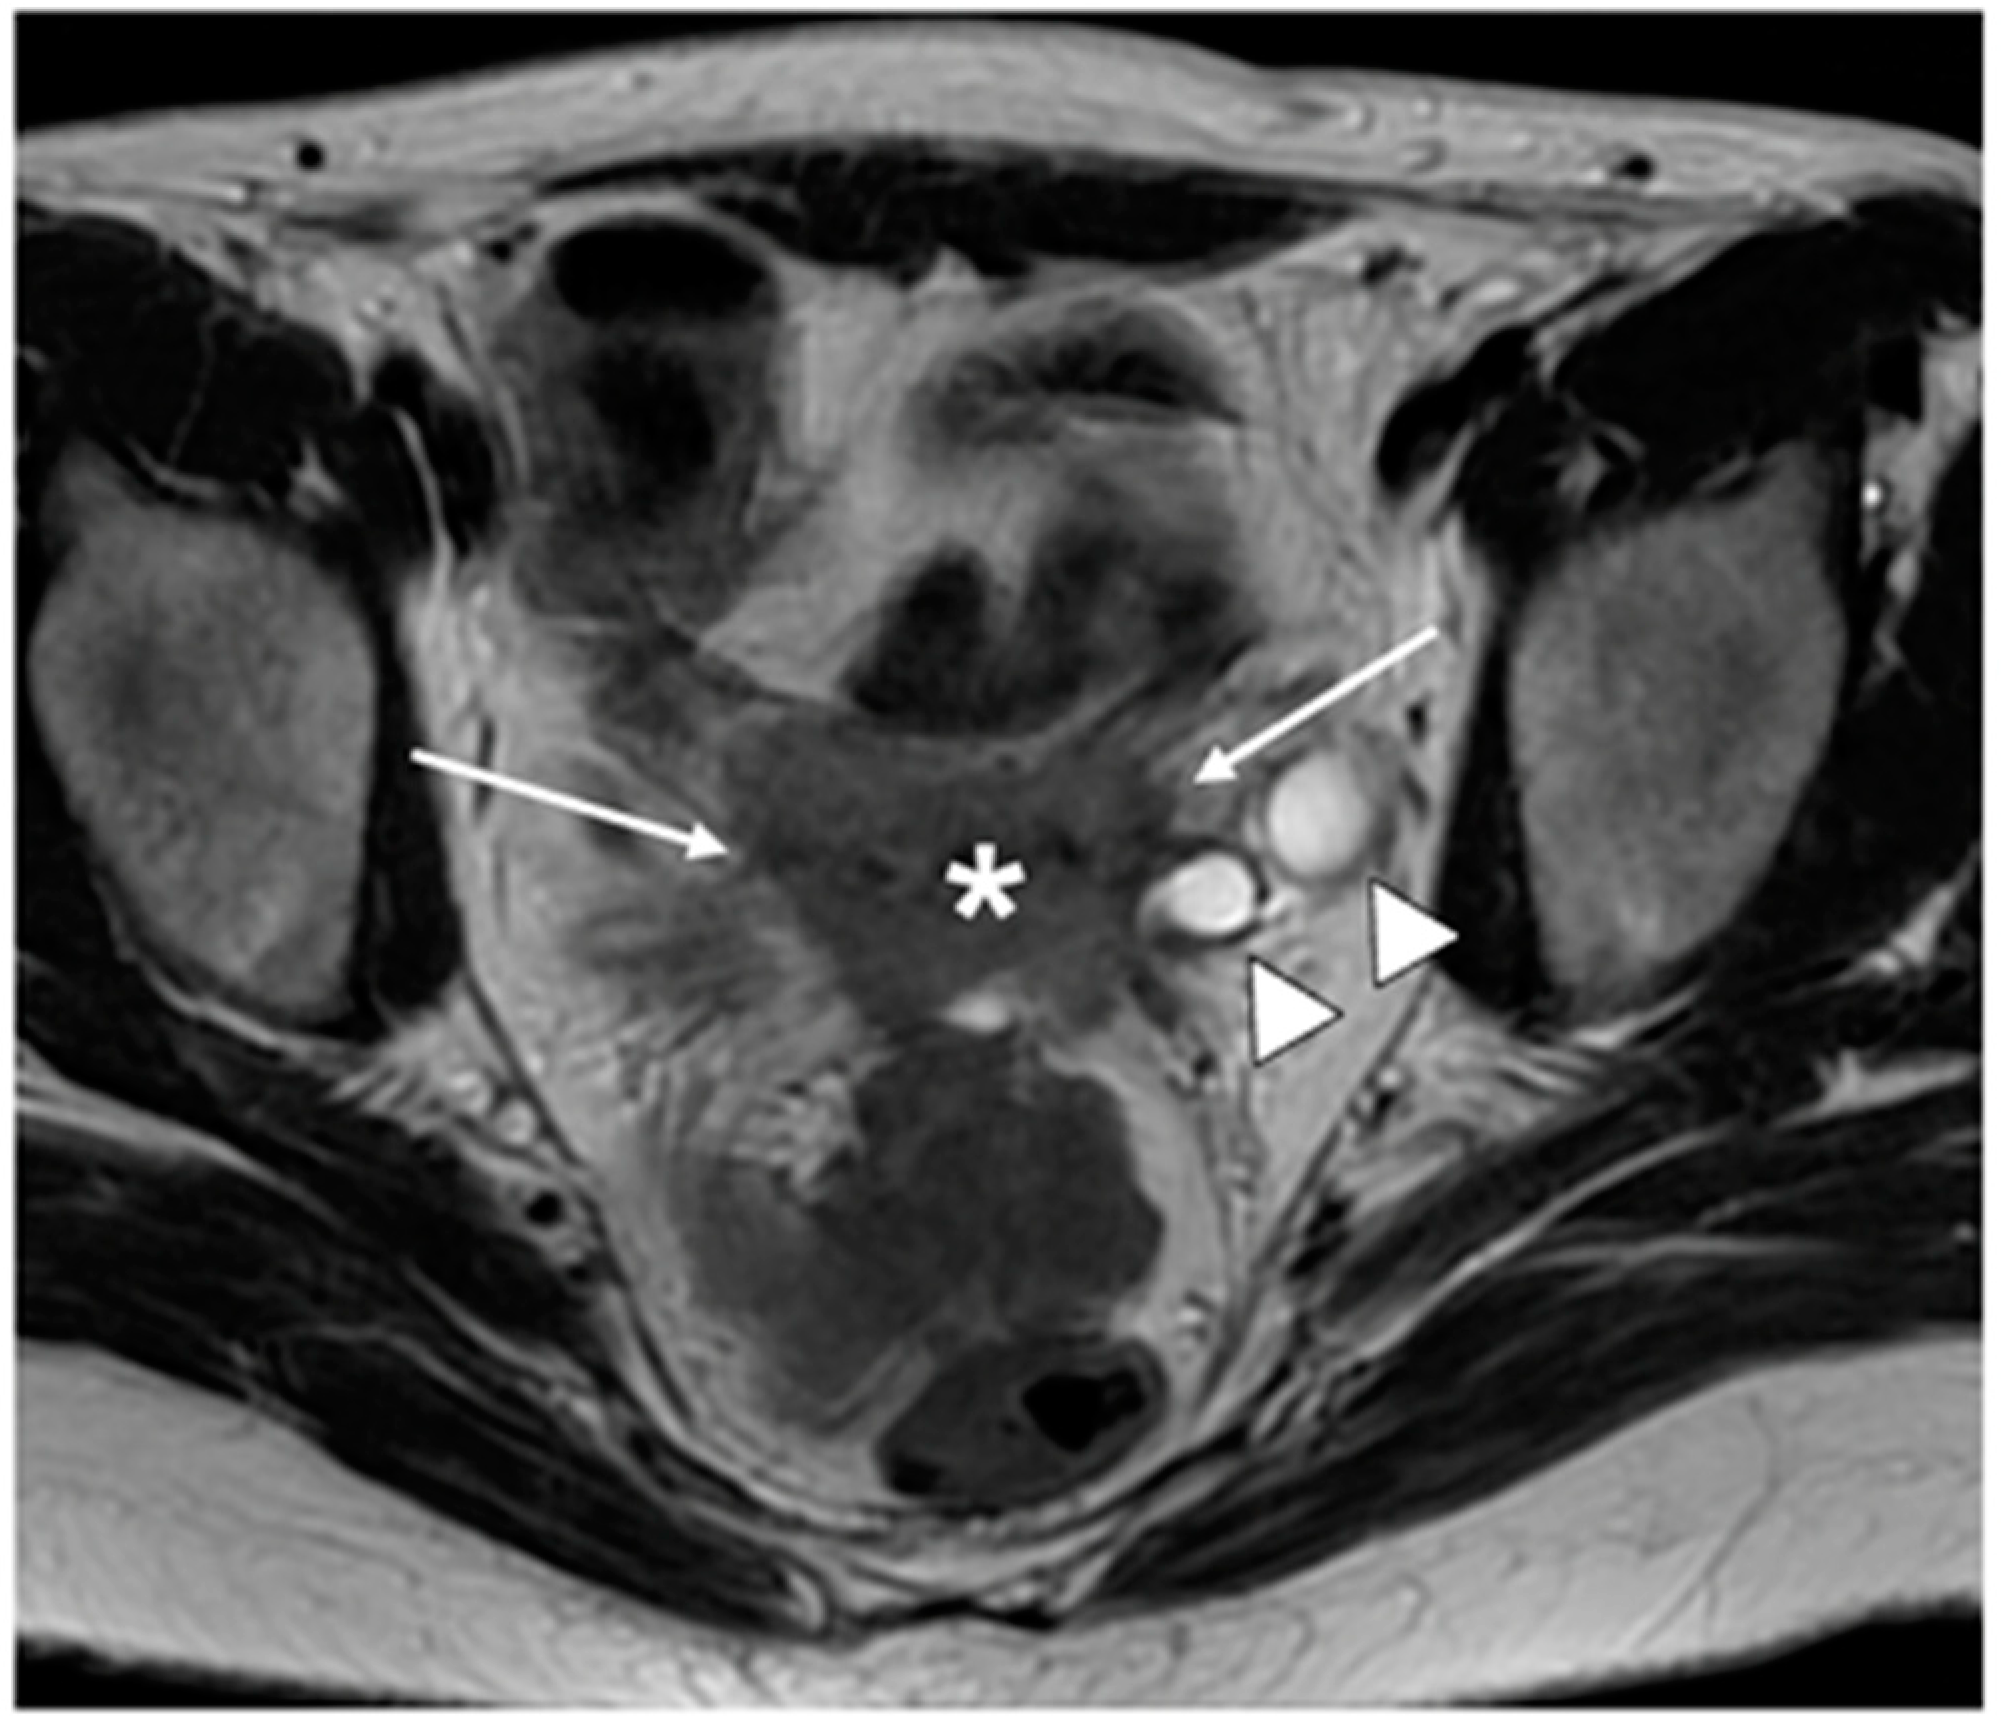

| IIIC | Involvement of pelvic and/or paraaortic lymph nodes |

| IIIC1 | Pelvic lymph node metastasis only |

| IIIC2 | Paraaortic lymph node metastasis |